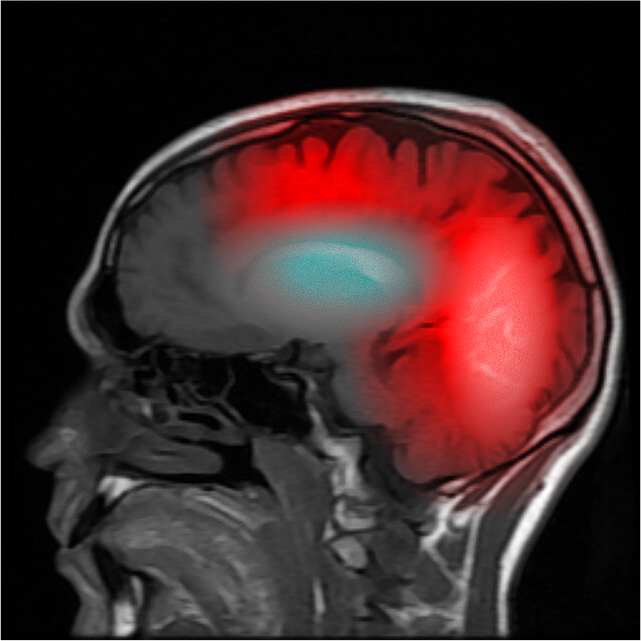

2015年2月5日 – 实验 – Owen Parsons的超常幽灵成像学检测

目标:确认SCP-9100现象成因是否为低等级幽灵实体附身。

方法:用Eckhart-Mendel法进行超常幽灵成像(PSG)。

主要结果:

Owen Parsons的EMPSG

- EMPSG成像显示,Parsons的脑部存在极微弱的幽灵活动,覆盖于Parsons的自然脑部活动之上。

- 该幽灵活动的模式与人类意识相同,这是人类幽灵的附身案例中的典型状况。

- 由此可确定SCP-9100是一种低等级幽灵实体。目前尚无法解释这些幽灵反常的行为模式。

- 基于以上结果,Owen Parsons被编号为SCP–9100-A1。